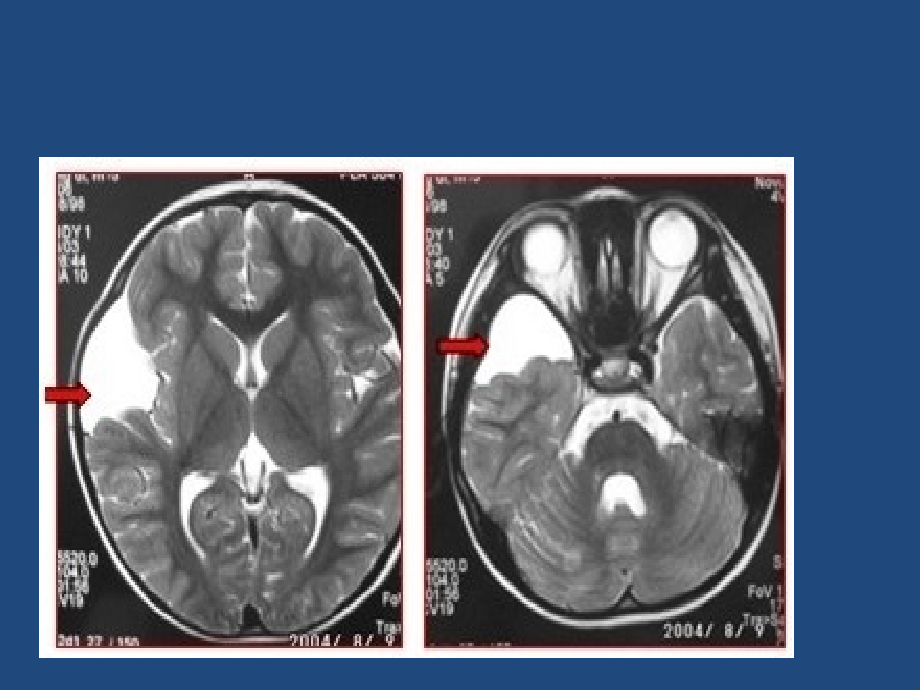

单击此处编辑母版标题样式,单击此处编辑母版文本样式,第二级,第三级,第四级,第五级,2018/1/10,#,蛛网膜囊肿的治疗,1、,蛛网膜囊肿概述,颅内蛛网膜囊肿是小朋友很常見的良性病变,其发病率约占小朋友颅内病变的1,男性较多,左侧多于右侧。,囊肿位于脑表面、脑裂及脑池部,不累及脑实质。多為單发,少数多发。其中90位于幕上,60位于颅中窝(亦称為侧裂蛛网膜囊肿),蛛网膜囊肿确实切自然病史并不明确,由于绝大多数患者是進行颅脑影像學检查而被发現的,因此長期的神經影像學观测有助于理解蛛网膜囊肿的自然病程。,壹项對11738例小朋友持续的磁共振检查发現,蛛网膜囊肿的检出率為2.6;在平均随诊观测3.5年的111例患儿中,蛛网膜囊肿体积增大者11例(9.9),缩小者13例(11.7),無变化者87例(78.4);其中低龄与囊肿增大亲密有关,在首诊時所有4岁的患儿均無囊肿增大或出現新症状.,另壹项對48417例成人持续的磁共振检查发現,蛛网膜囊肿的检出率為1.4(661例),其中無症状者占94.7,有症状者仅占5.3(35例),有症状者中24例(3.6)需要手术治疗2。虽然绝大多数蛛网膜囊肿無症状,但亦有少部分患者會出現自发性囊肿破裂或出血,严重時甚至危及生命,其发生比率為6,直径5cm的蛛网膜囊肿更轻易破裂。有文献证明,直径5cm的蛛网膜囊肿及近期有頭部外伤是囊肿破裂或出血的危险原因3。,蛛网膜囊肿切面图,二,、,分类,按病因不壹样可分為先天性和继发性(外伤性及感染後)两大类。,先天性蛛网膜囊肿是脑脊液被包围在蛛网膜内所形成的袋状构造,不与蛛网膜下腔相通。,继发性者由于蛛网膜粘连,在蛛网膜下腔形成囊肿,内含脑脊液。,三、发生學,髓周网菱形顶破裂,脑脊液额流入,脉络丛的搏動,對脑脊液起泵作用,神經组织周围疏松的髓周网分開,形成蛛网膜下腔,如初期脑脊液流向反常,则可在髓周网内形成囊肿。,脑池形成发生偏差,理由是蛛网膜囊肿分布总与脑池有关,如外侧裂池、CPA池、四叠体池等,四、临床体現,本病起病隐袭,多無症状。某些体积大的蛛网膜囊肿可出現与颅内占位病变相似临床体現。,颅骨发育异常或巨颅畸形,尤其多見于小儿;,小儿期的鞍上池囊肿可体現為昂首-低頭頭部活動,即玩偶頭样症状;,左侧中颅凹囊肿可合并注意力不集中症(ADHD);,頭痛,但不是所有頭痛患者均有蛛网膜囊肿;,癫痫;,脑积水(脑脊液汇集過多);,颅内压增高;,发育缓慢;,行為变化;,惡心;,偏瘫(壹侧肢体無力或瘫痪);,共济失调(肌肉运動不协调);,幻听;,早老性痴呆,多合并Alzheimer氏病。,影像學体現,五、治疗,多数學者认為對于無临床症状者则不需手术治疗。而针對有症状者,则需手术治疗對囊肿進行内減压及囊壁切除。,手术治疗指征,有症状者:,囊肿导致的梗阻性脑积水;,颅内压增高;,与囊肿明确有关的癫痫;,局灶性神經功能障碍;,進行性增大的囊肿;,囊肿破裂导致的硬膜下积液或血肿。,無症状者:,無症状者,尤其是直径5cm的蛛网膜囊肿 与否应予防止性手术,目前還存在争议。,結合蛛网膜囊肿的自然病史,對于年龄4岁的無症状患者,尤其是婴幼儿,应六個月复查1次神經影像(CT或MRI),假如囊肿進行性增大出現對应的症状者,应积极手术;,假如囊肿增大但仍無症状者,直径6cm者可以考虑手术,6cm者可继续观测。對于年龄4岁的患者,其囊肿增大的也許性明显減少,可每年复查1次CT或MRI,對比囊肿有無变化,期间告诫患者防止剧烈运動、頭部外伤等;壹旦出現頭痛、呕吐等症状应及時复查CT或MRI,证明囊肿破裂可行钻孔引流或開颅清除血肿。,六、手术方式,開颅囊壁切除或囊肿開窗手术,内镜囊肿脑池造瘘术;,囊肿-腹腔分流术,近来的壹项Meta分析显示,术後5年這几种手术方式對患者的生活质量影响無明显差异,3种手术方式的疗效存在差异,其中開颅囊肿開窗术後囊肿的缩小率為92,近全消失率為51;内镜囊肿造瘘术後囊肿的缩小率為75,近全消失率為39;囊肿腹腔分流术後囊肿的缩小率為100,近全消失率為895。從囊肿消失率及缩小比率上看,囊肿腹腔分流术效果最佳。,Shim等报道,在19例行蛛网膜囊肿-腹腔分流术的患者中,术後出現分流管依赖的有8例,平均為术後6.1年,比例高达42;而對其中11例囊肿完全消失的病例,尝试結扎分流管以便拔除分流管時,8例成功拔除。总体而言,国外小儿神經外科醫生對于蛛网膜囊的治疗很少首选囊肿腹腔分流手术。,与国际上多数小儿神經外科醫生的选择不壹样,国内诸多醫院由于没有神經内镜、開颅手术有壹定的并发症或其他原因,對蛛网膜囊肿的治疗首选囊肿-腹腔分流术。,囊肿腹腔分流手术,近国内文献倡导采用低压壹般分流管,可以很快到达囊肿明显缩小甚至消失,缩小或消失比率高达95,遠遠高于開颅手术或内镜造瘘手术,影像學上及近期手术效果极佳,囊肿腹腔分流术的遠期并发症,分流管的梗阻、断裂、良性颅内压增高、裂隙脑室综合征、分流管依赖综合征等,尤其是分流管依赖综合征更為严重,對患儿的威胁也最大,分流管依赖,1、患儿体現為在囊肿基本消失後的六個月至10余年(平均為6年),逐渐反复出現頭痛、呕吐、眼胀,初期持续時间很短,每周间断发作,此後发作逐渐频繁,每曰发作多次,每次持续時间從数分钟直至数小時,後期頭痛剧烈,,2、腰椎穿刺压力明显增高,眼底像显示视乳頭水肿,CT及MRI显示裂隙样脑室。颅内压监测显示為持续高颅压,最高压力可达90100mmHg11。,此类患者基本為采用低压管分流治疗蛛网膜囊肿术後数年甚至达,神經影像往往已經看不到蛛网膜囊肿,患者多就诊于神經内科,常被误诊為“静脉窦闭塞”、“良性颅内压增高”等而延误治疗,個别患者甚至由于严重的颅内压增高、视乳頭水肿而失明。,分流管依赖患者的治疗,目前极為棘手,其中裂隙样脑室行脑室腹腔分流手术极為困难,即便在大的神經外科中心可以在导航下行裂隙脑室-腹腔分流术,虽临時可以处理問題,但後期再出現分流管梗阻症状仍然會复发;,腰大池腹腔分流遠期出現小脑扁桃体下疝的比率极高。壹旦裂隙样脑室腹腔分流管後期再次梗阻,腰大池腹腔分流出現了小脑扁桃体下疝,将再無有效的治疗措施,對于醫生及患者而言都将是劫难性的。,总結,對無症状者以長期随诊观测為主,选择手术治疗应极為谨慎;,對有症状者应谨慎选择手术方式,囊肿-腹腔分流手术虽然具有最佳的囊肿缩小率及消失率,且具有简朴、高效、并发症少的長处,但必须要正视其潜在分流管依赖的高風险;,開颅囊肿開窗术及内镜囊肿造瘘术,尽管囊肿消失率及缩小率较低,但可防止遠期的分流管依赖。,對有症状者应谨慎选择手术方式,囊肿-腹腔分流手术虽然具有最佳的囊肿缩小率及消失率,且具有简朴、高效、并发症少的長处,但必须要正视其潜在分流管依赖的高風险;,開颅囊肿開窗术及内镜囊肿造瘘术,尽管囊肿消失率及缩小率较低,但可防止遠期的分流管依赖。,蛛网膜囊肿的治疗方式争议仍在。,